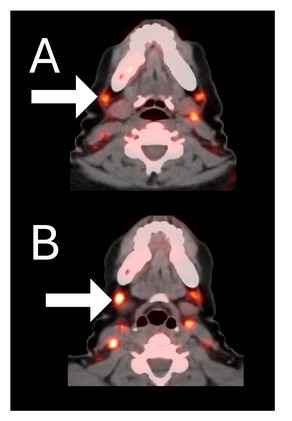

A 44-year-old woman with ER+/PR+/HER2- metastatic breast cancer, previously treated with 5 prior lines of therapy. At baseline, she presented with metastases to the spine. She completed 6 cycles of therapy achieving stable disease as her best response and remains in survival follow-up 27 months after study entry.

Before BriaCell Treatment Image A: CD8 ImmunoPET image

Pre-treatment imaging of cervical (neck) lymph nodes with moderate uptake indicating presence of some CD8+ cytotoxic (“killer”) T cells.

After BriaCell Treatment Image B: CD8 ImmunoPET image

Post treatment enhancement of cervical (neck) lymph nodes indicating immune system activation and increased presence of CD8+ cytotoxic T cells.

Example 2 Images (Patient 15-005): CD8 ImmunoPET images pre (A) and post (B) Bria-IMT treatment